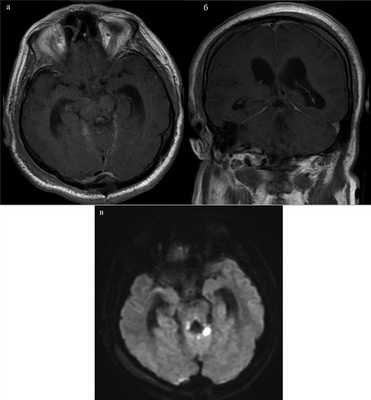

По данным МРТ головного мозга от 21.09.17, остатков опухоли в режиме Т1 не обнаружено (рис. 3, а, Рис. 3. МРТ после операции. а, б — томограммы, выполненные в режиме Т1, остатки опухоли не обнаружены; в — в режиме DWI визуализируется небольших размеров очаг ишемии в области верхней ручки мозжечка слева. б). В режиме DWI визуализировался небольших размеров очаг ишемии в области верхней ручки мозжечка слева (см. рис. 3, в).